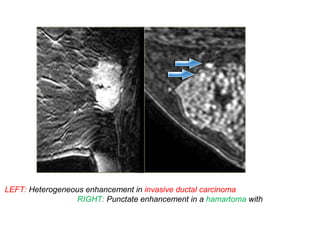

LEFT: Heterogeneous enhancement in invasive ductal carcinoma

RIGHT: Punctate enhancement in a hamartoma with